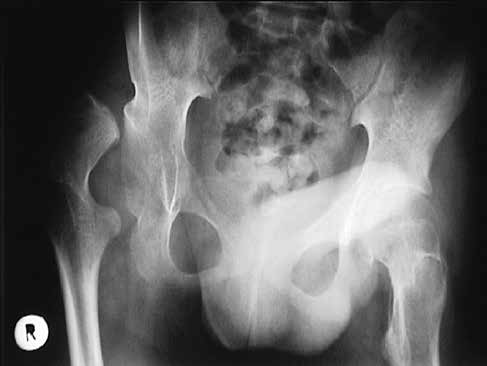

Rekonstruktiver Hüfteingriff

Der rekonstruktive Hüfteingriff mit offener Reposition ist nach Erfahrung internationaler und auch unseres Zentrums bei Hüftluxationen Erwachsener gegenüber anderen Verfahren wie Resektionen zu bevorzugen (Abb. 5 u. 6).Frühere Mobilisierung ohne Gipslagerung brachte in den vergangenen Jahren einen großen Vorteil für die betroffenen Kinder und ihre Familien.

Postoperativ sind eine frühe Mobilisierung, eine symmetrische Lagerung im Sitzen und Liegen sowie eine langsam beginnende regelmäßige Steh- und Gehtherapie mit neuen Bewegungstrainern anzustreben.